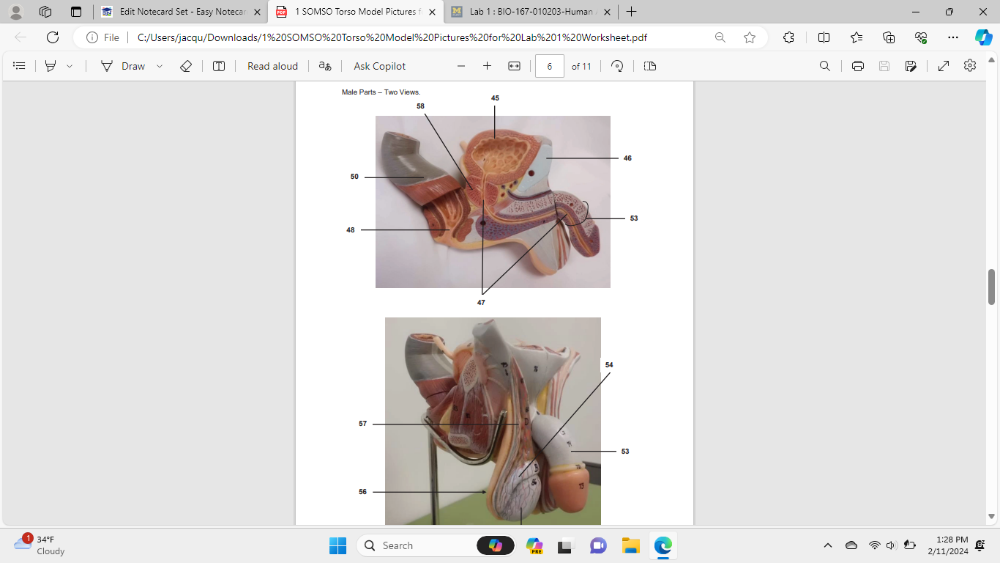

Identify the specific organ labeled 45

urinary balder

Identify the specific part of the bone labeled 46

pubic symphysis

Identify the specific organ labeled 47

urethra

Identify the specific organ (be specific) labeled 50

rectum

Identify the specific organ labeled 53

Penis

Identify the specific organ labeled 54

right epididymis

Identify the specific organ labeled 55

right testis

Identify the specific organ/structure labeled 56

scrotum

Identify the specific organ labeled 57

right vas deferens

Identify the specific organ labeled 58

prostate gland